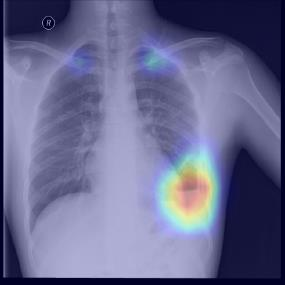

Chest X-ray (CXR) is the most typical diagnostic X-ray examination for screening various thoracic diseases. Automatically localizing lesions from CXR is promising for alleviating radiologists' reading burden. However, CXR datasets are often with massive image-level annotations and scarce lesion-level annotations, and more often, without annotations. Thus far, unifying different supervision granularities to develop thoracic disease detection algorithms has not been comprehensively addressed. In this paper, we present OXnet, the first deep omni-supervised thoracic disease detection network to our best knowledge that uses as much available supervision as possible for CXR diagnosis. We first introduce supervised learning via a one-stage detection model. Then, we inject a global classification head to the detection model and propose dual attention alignment to guide the global gradient to the local detection branch, which enables learning lesion detection from image-level annotations. We also impose intra-class compactness and inter-class separability with global prototype alignment to further enhance the global information learning. Moreover, we leverage a soft focal loss to distill the soft pseudo-labels of unlabeled data generated by a teacher model. Extensive experiments on a large-scale chest X-ray dataset show the proposed OXnet outperforms competitive methods with significant margins. Further, we investigate omni-supervision under various annotation granularities and corroborate OXnet is a promising choice to mitigate the plight of annotation shortage for medical image diagnosis.